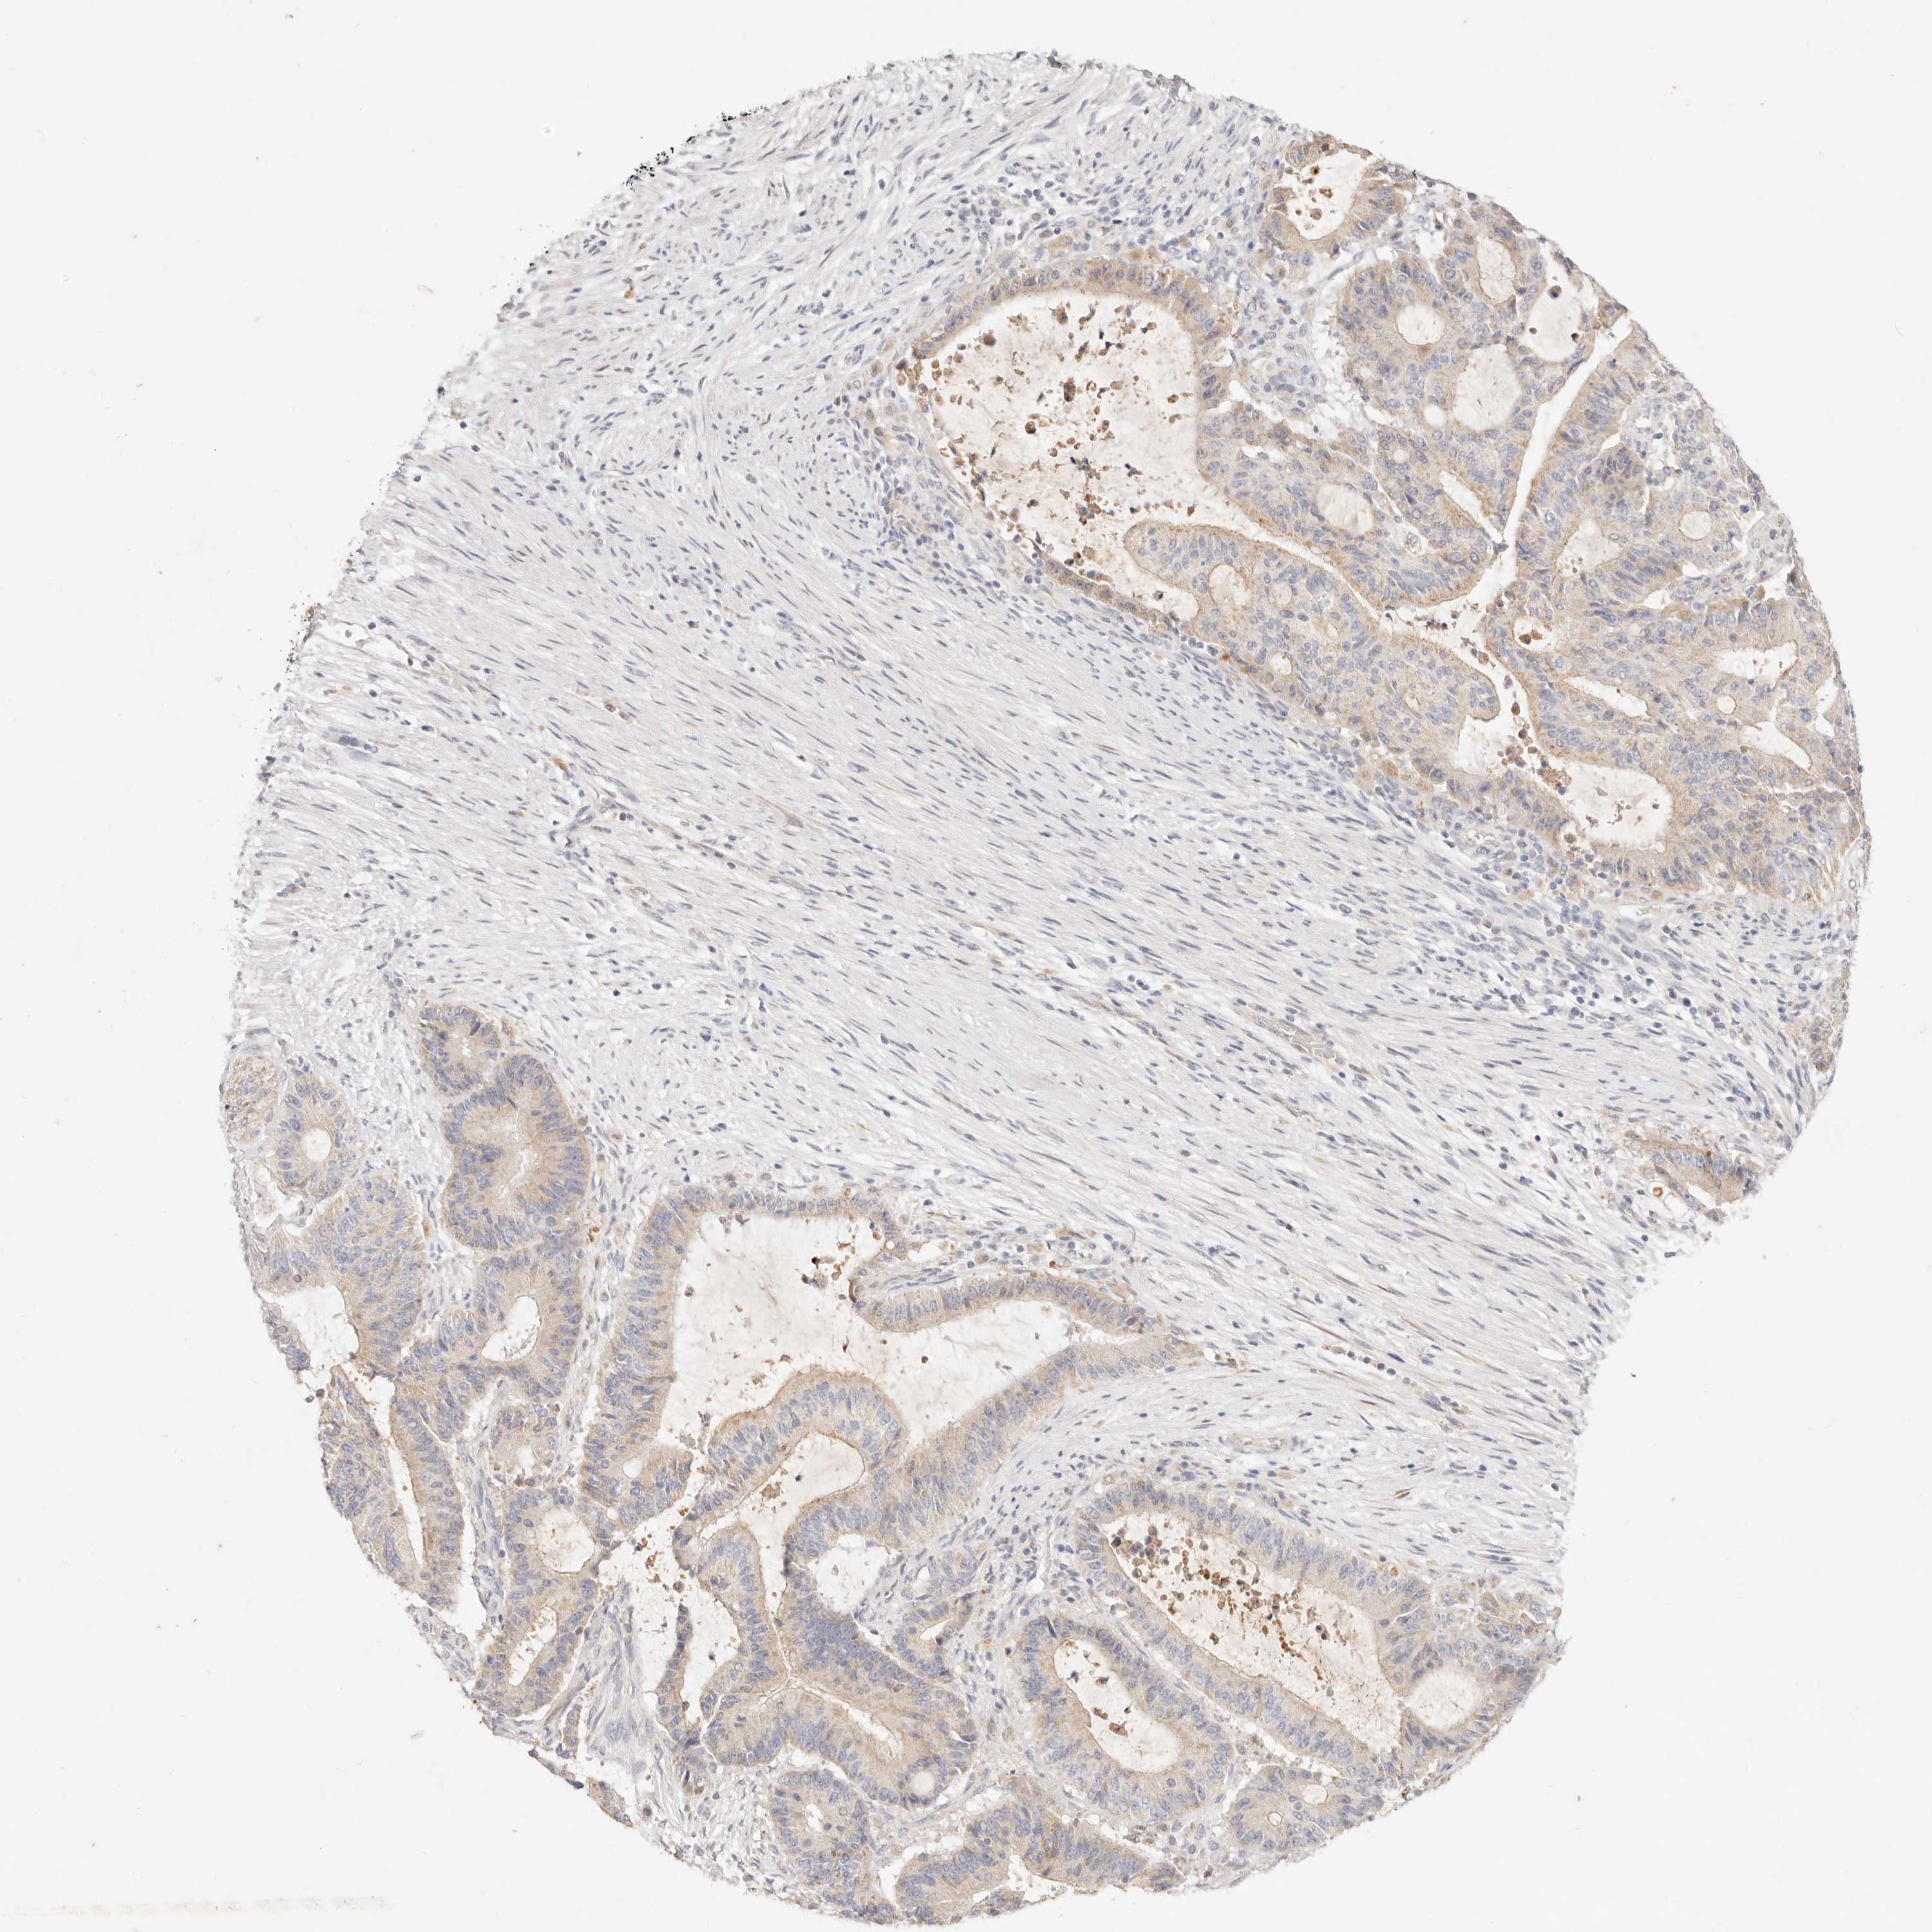

LIVER CANCER - Protein expressioni

A mouse-over function shows sample information and annotation data. Click on an image to view it in a full screen mode. Samples can be filtered based on level of antibody staining by selecting one or several of the following categories: high, medium, low and not detected. The assay and annotation is described here.

Note that samples used for immunohistochemistry by the Human Protein Atlas do not correspond to samples in the TCGA dataset.

Antibody stainingi

Antibody staining in the annotated cell types in the current human tissue is reported as not detected, low, medium, or high, based on conventional immunohistochemistry profiling in selected tissues. This score is based on the combination of the staining intensity and fraction of stained cells.

Each image is clickable and will lead to virtual microscopy that enables deeper exploration of all samples and also displays staining intensity scores, fraction scores and subcellular localization as well as patient and tissue information for each sample.

Antibody HPA021192

Antibody HPA021195

Antibody HPA028759

Antibody CAB021094

Staining

High

Medium

Low

Not detected

Intensity

Strong

Moderate

Weak

Negative

Quantity

>75%

75%-25%

<25%

None

Location

Nuclear

Cytoplasmic/membranous

Cytoplasmic/membranous,nuclear

Cholangiocarcinoma

Carcinoma, Hepatocellular, NOS